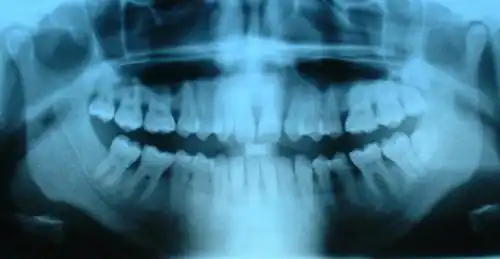

Radiographie panoramique permettant de voir l'ensemble de la denture (carie en distal de la dent no 35).